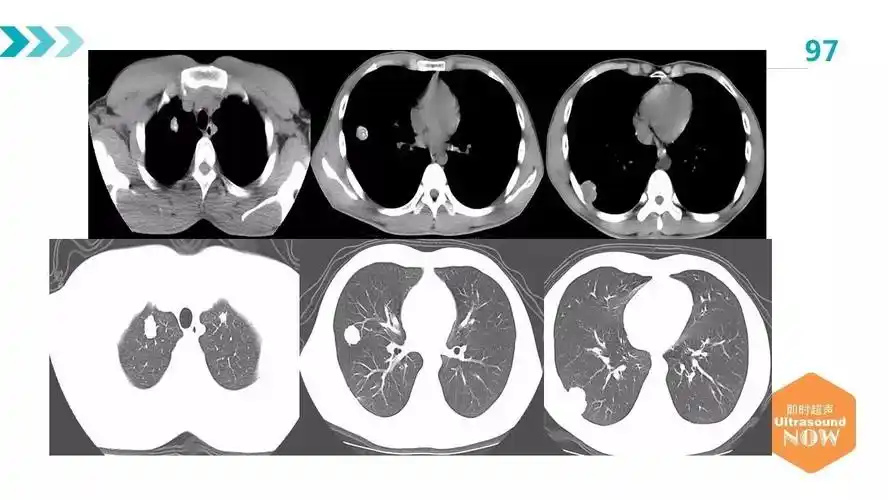

肺包虫病的影像学诊断及误诊分析

肺包虫病一例——黄超,新疆职业病医院

胸部,腹部ct回报:肝脏,右肺及腹腔,盆腔多发巨大囊性病灶,符合包虫病

下面这个肺包虫病,寄生虫都裂开了,形成空洞,但是ct表现还是四不像,你